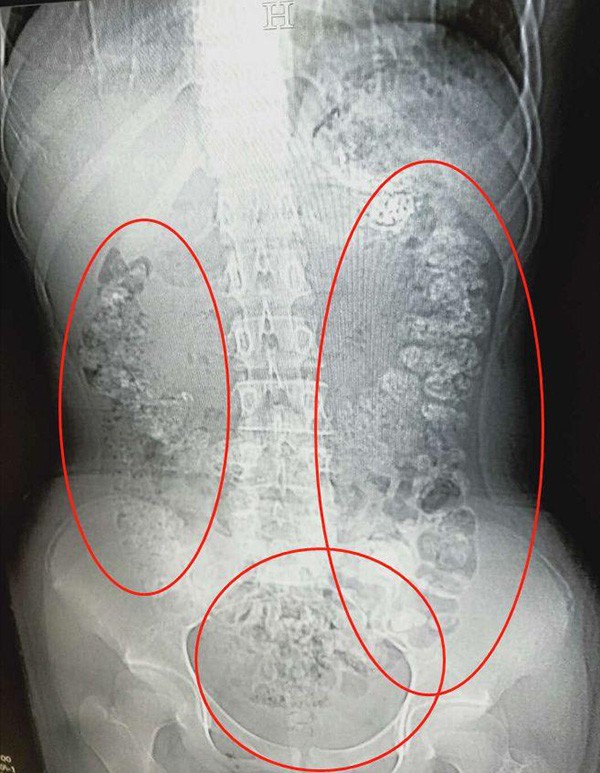

掃瞄結果令人大吃一驚,小沈的胃部、橫結腸、升結腸、降結腸、乙狀結腸,甚至一直到肛門,都發現了顆粒狀陰影,數量更超過100粒。後來醫生詢問小沈最近有沒有進食不易消化的食物。小沈才吞吞吐吐說出5天前曾喝過珍珠奶茶。